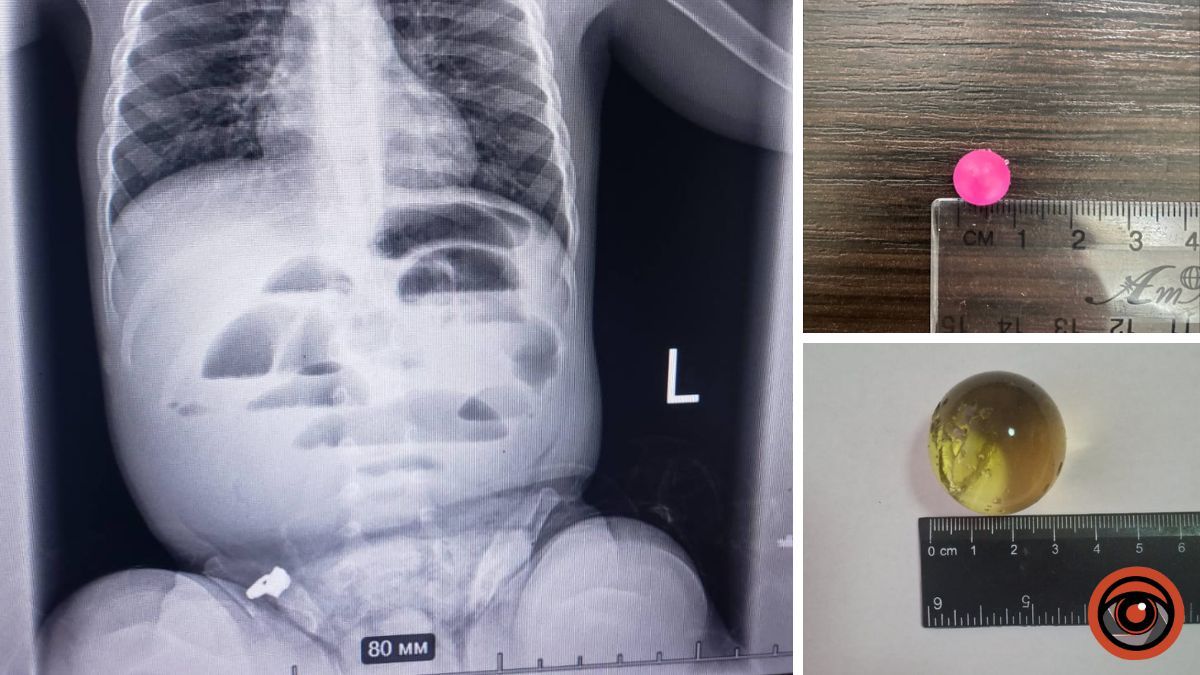

У Дніпрі дитина віком 1 рік і 8 місяців проковтнула гідрогелеву кульку. Її доставили до лікарні з підозрою на кишкову непрохідність. Медики зробили рентген і побачили, що кишківник заблокований. Під час операції виявили, що кулька всередині розрослася до трьох сантиметрів і перекрила шлях їжі.

Лікарі вчасно дістали кульку та наклали шви. Дитину перевели до реанімації. Медики нагадують батькам: такі кульки небезпечні, бо можуть рости всередині організму.